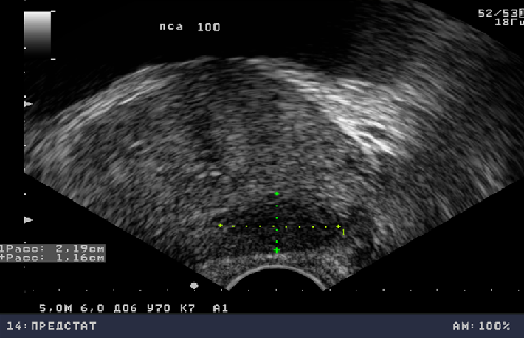

Эхогенность простаты

Эхогенность простаты 114 фотографий